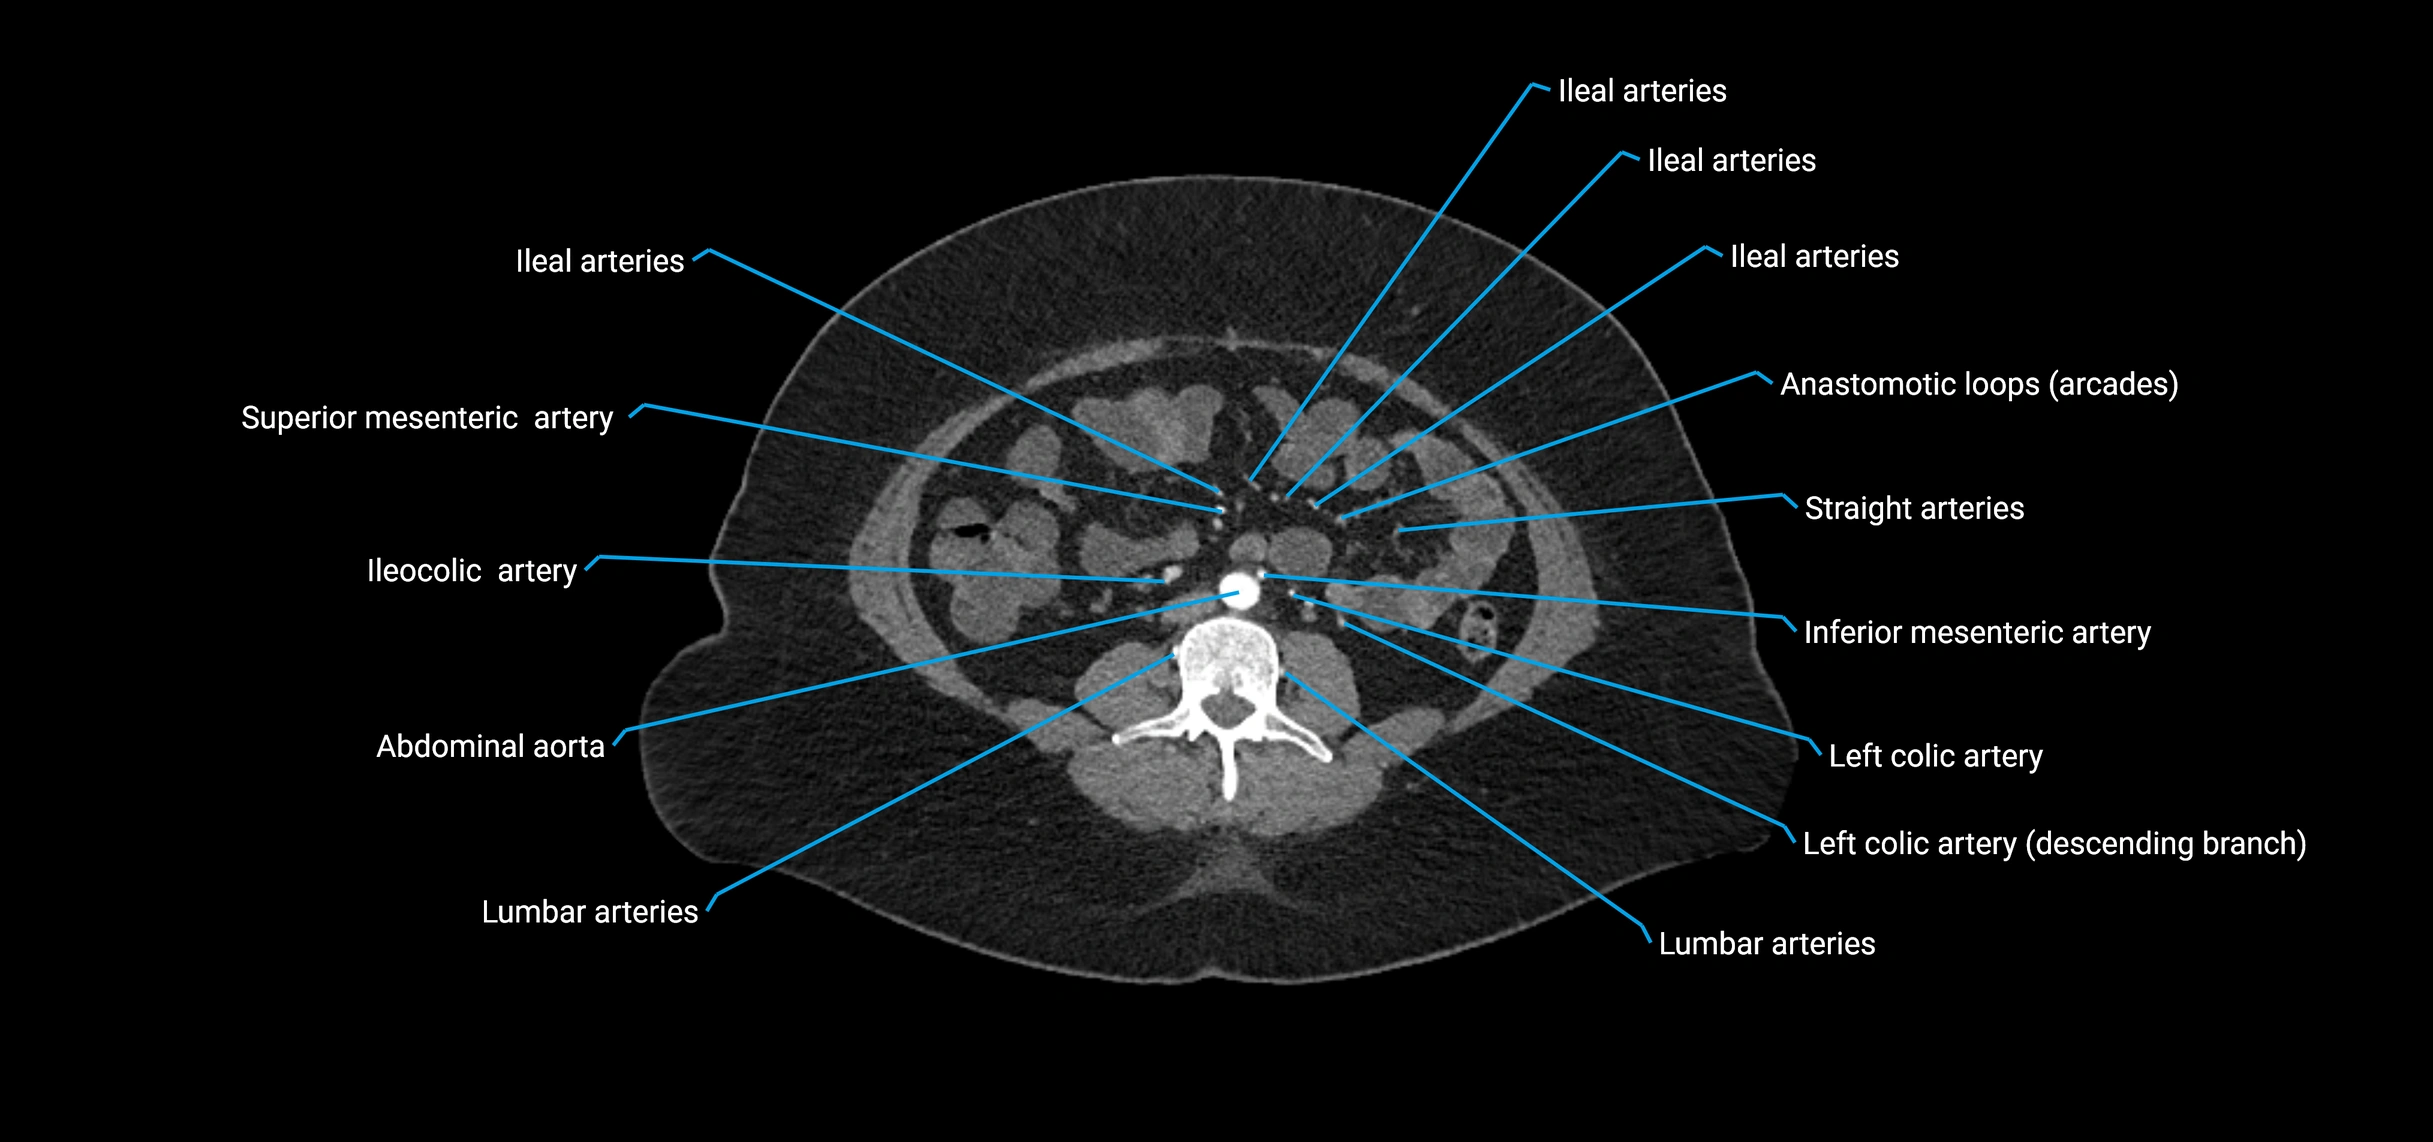

CT Appearance

Non-contrast CT:

• Appears as a tubular soft tissue structure anterior to vertebral bodies

• Calcified atherosclerotic plaques appear as hyperdense foci along the wall

• Useful for screening abdominal aortic aneurysm (AAA) size and mural calcification

Contrast-enhanced CT (CTA):

• Gold standard for abdominal aortic imaging

• Provides excellent detail of lumen, wall, aneurysm, thrombus, and branch vessels

• Multiplanar and 3D reconstructions help in aneurysm measurement, stent graft planning, and dissection evaluation

• Detects acute rupture, traumatic injury, or occlusion with high sensitivity

CT images

image